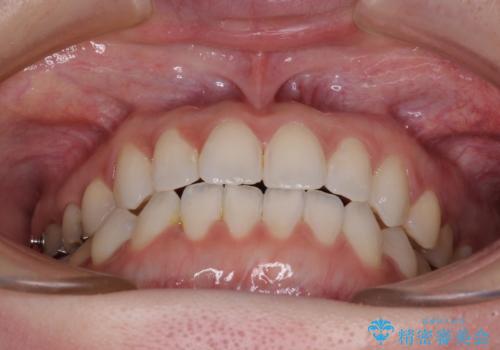

前歯のデコボコをすっきりと インビザライン矯正

- 2年5ヶ月

- 前歯のデコボコを治したいとのことで来院された患者様です。

下顎が前方位にある方であったため、下顎の歯列全体の後方移動とIPR(歯と歯の間を削る)によってデコボコが解消するように設計し、インビザラインにより治療を行うこととしました。

装着時間が守れず、当初の予定よりも長期間必要となりました。